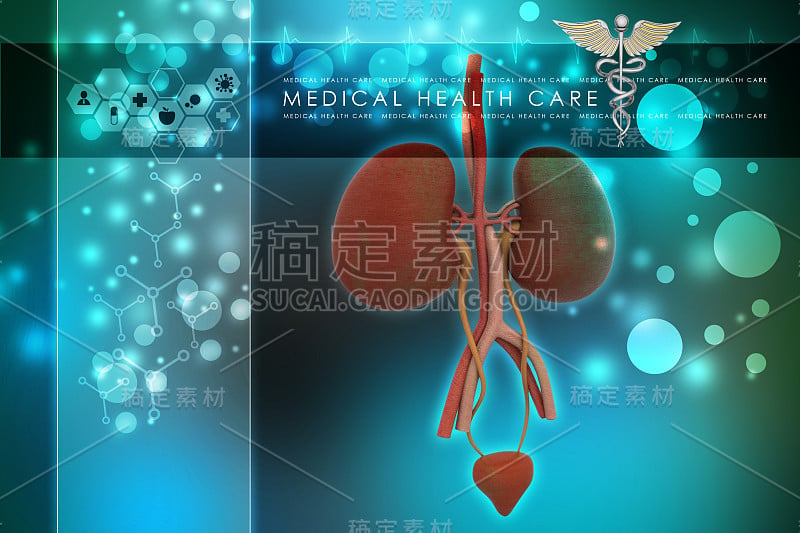

泌尿系统详情

JPG

泌尿系统详情

JPG